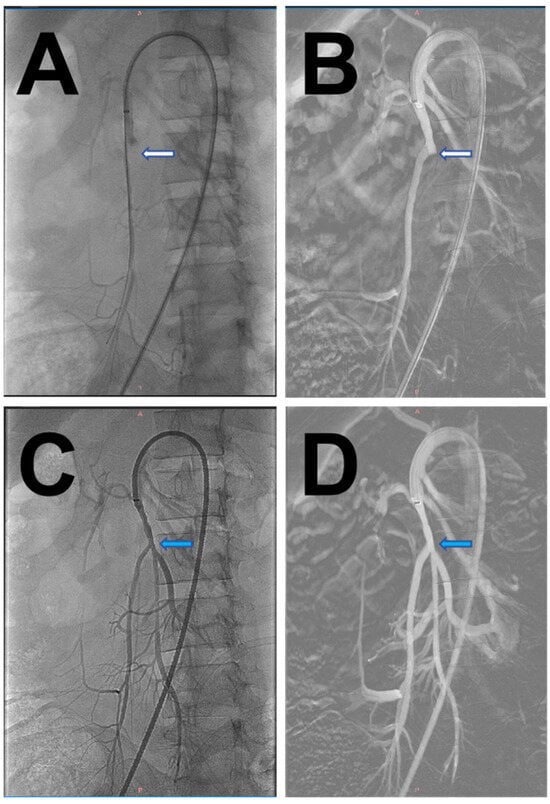

2. Case Report